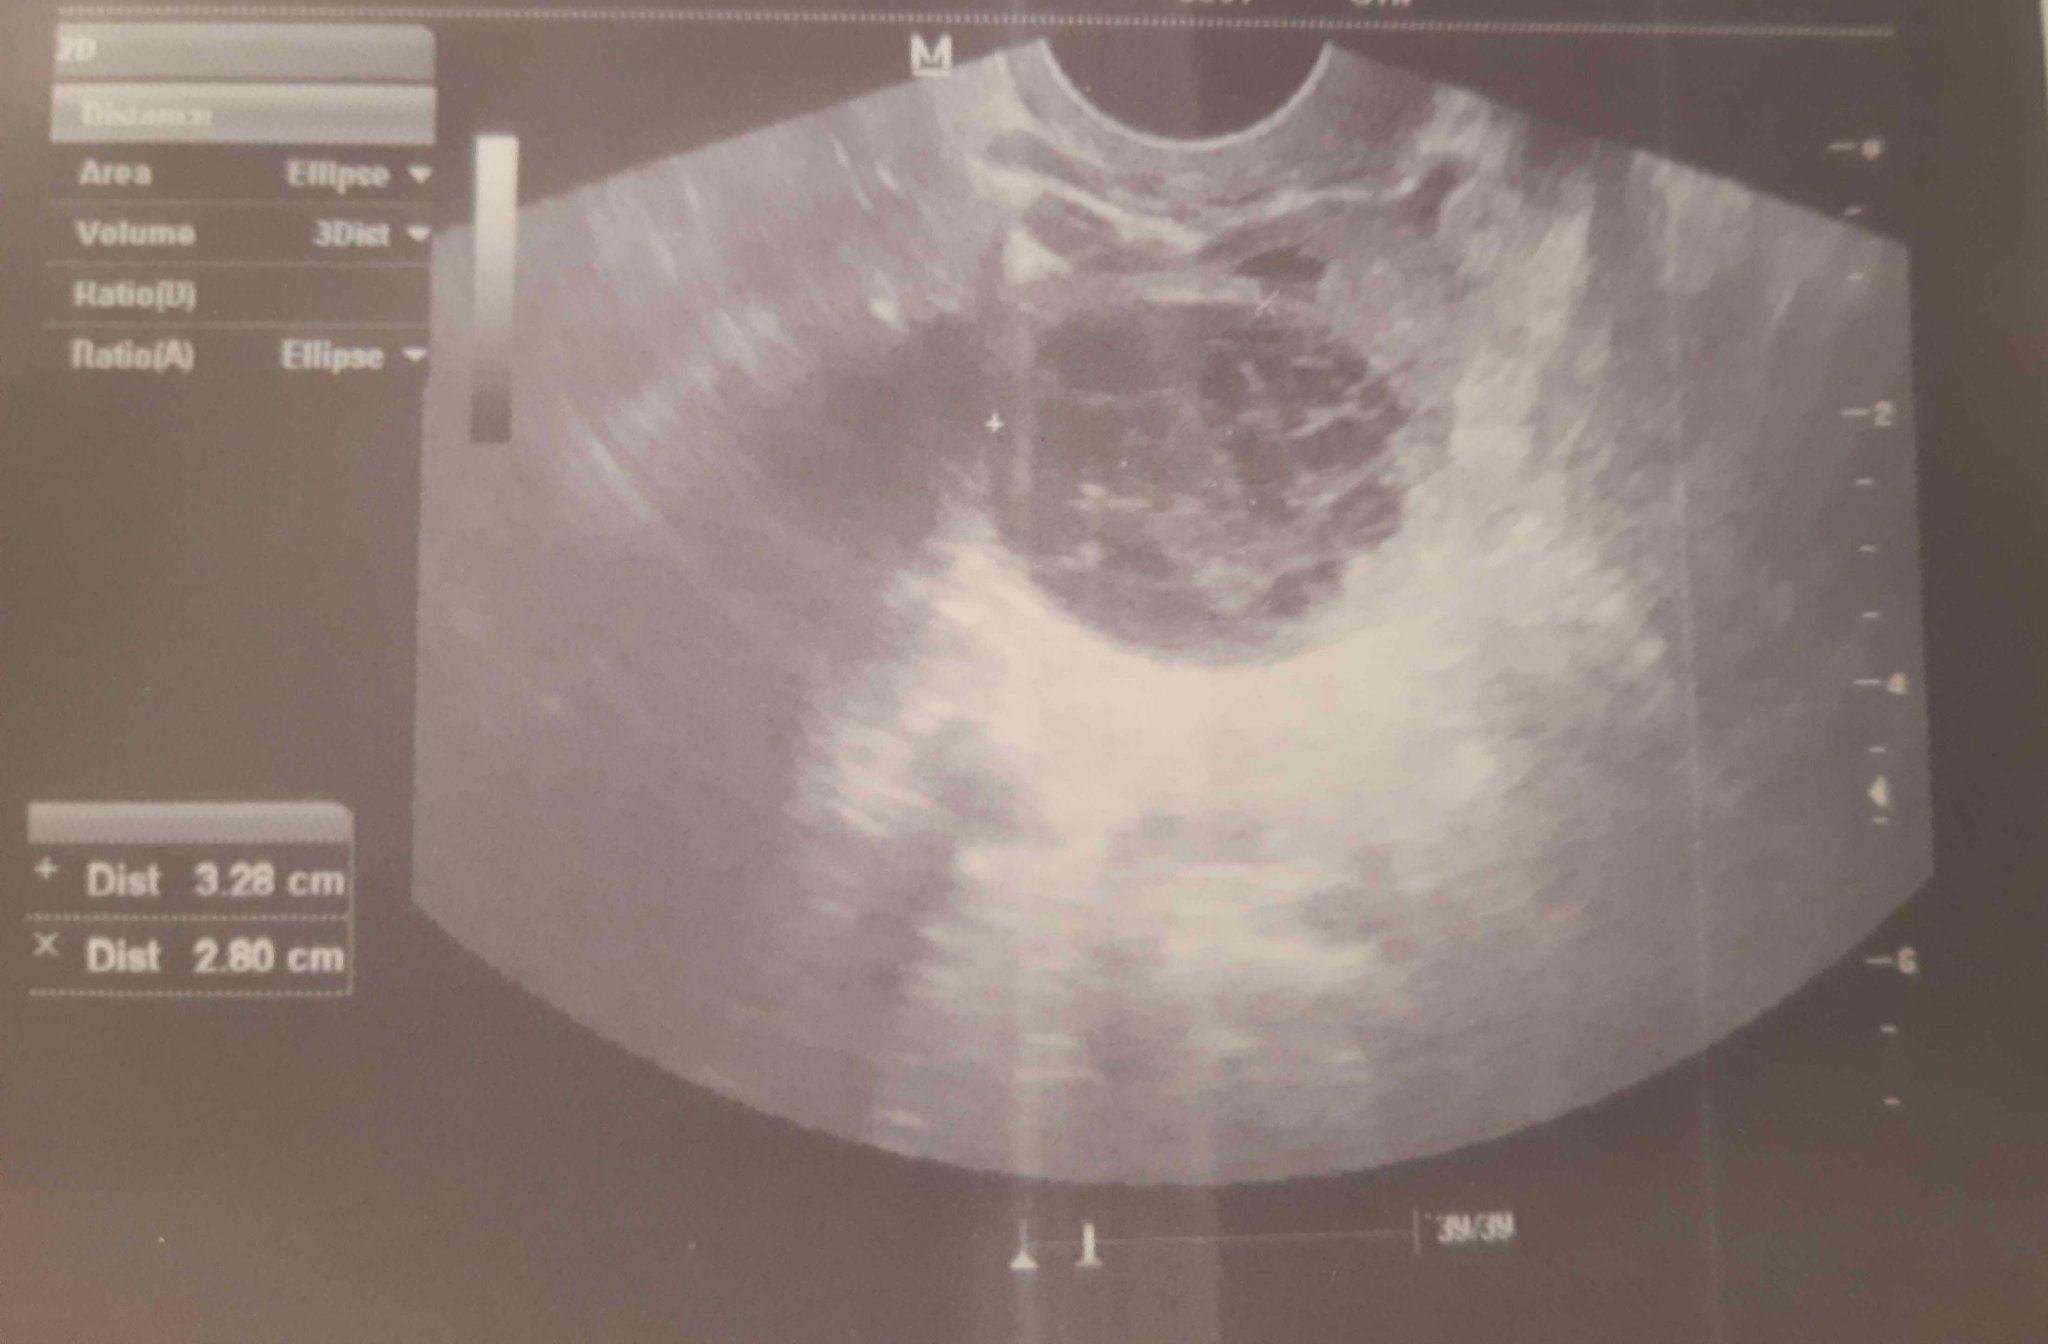

Знам, че вие няма как да ми кажете и не сте лекари, утре със сигурност при Налбански ще разбера каква е кистата. Но ми я откриха днес, докторката ми каза, че е фоликулярна и ще изчезне след цикъл. Питах я дали не е ендо, тя ми казва, че не е, но на мен точно на такава ми прилича, защото не е бистра...вие какво мислите ?

Прилича ми на ендо, но може ехографа да не е много качествен. Пиши какво е казал Налбански.

И на мен ми прилича на ендо...ама докторката каза, че не е два пъти...искам да й повярвам, но днес ще стане ясно...Sad

Добри новини, не е ендометриозна киста, каза, че ще изчезне само Simple Smile